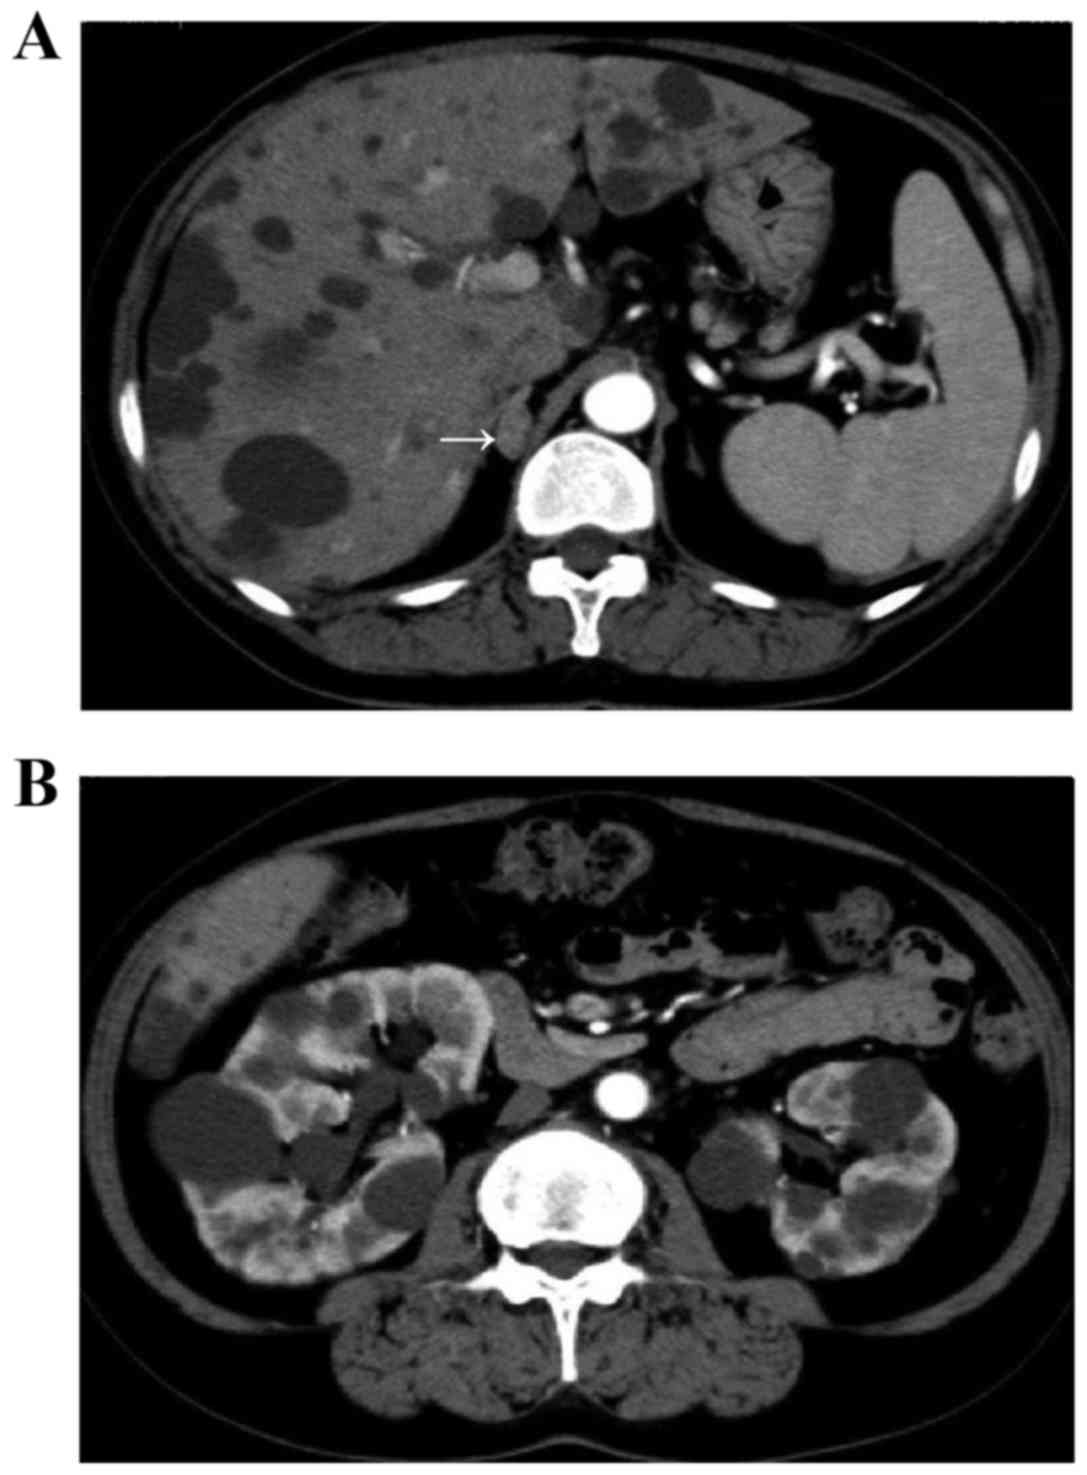

Plasma renin activity (PRA) was ≤0.1 ng/ml/h (normal range, 0.1–0.3 ng/ml/h), thus bisoprolol was discontinued to exclude a false low result. Oral iron supplements (100 mg/day) were administered, resulting in gradual improvement of anemia. Thereafter, a captopril (50 mg) stimulation test was conducted producing a low renin response (Table II; normal range, renin response >1.0 ng/ml/h, aldosterone-to-renin ratio (ARR) of 60 or 90 min <200). Abdominal computed tomography and magnetic resonance imaging revealed a right adrenal tumor ~1.0 cm in size and multiple cysts in the liver and kidneys (Fig. 1). The estimated volume of the bilateral kidneys was calculated using the volumetric method and the following formula: Volume = π/6x length × width × depth (9,10) and was determined to be ~705.4 ml.

Figure 1.

Abdominal computed tomography and magnetic resonance imaging. Abdominal computed tomography indicated (A) a right adrenal (arrow) tumor ~1.0 cm in size and multiple cysts in the liver and (B) the kidneys. (C) Abdominal T2-weighted coronal magnetic resonance image identified a right adrenal (arrow) tumor ~1.0 cm in size and multiple cysts in the liver and the bilateral kidneys.